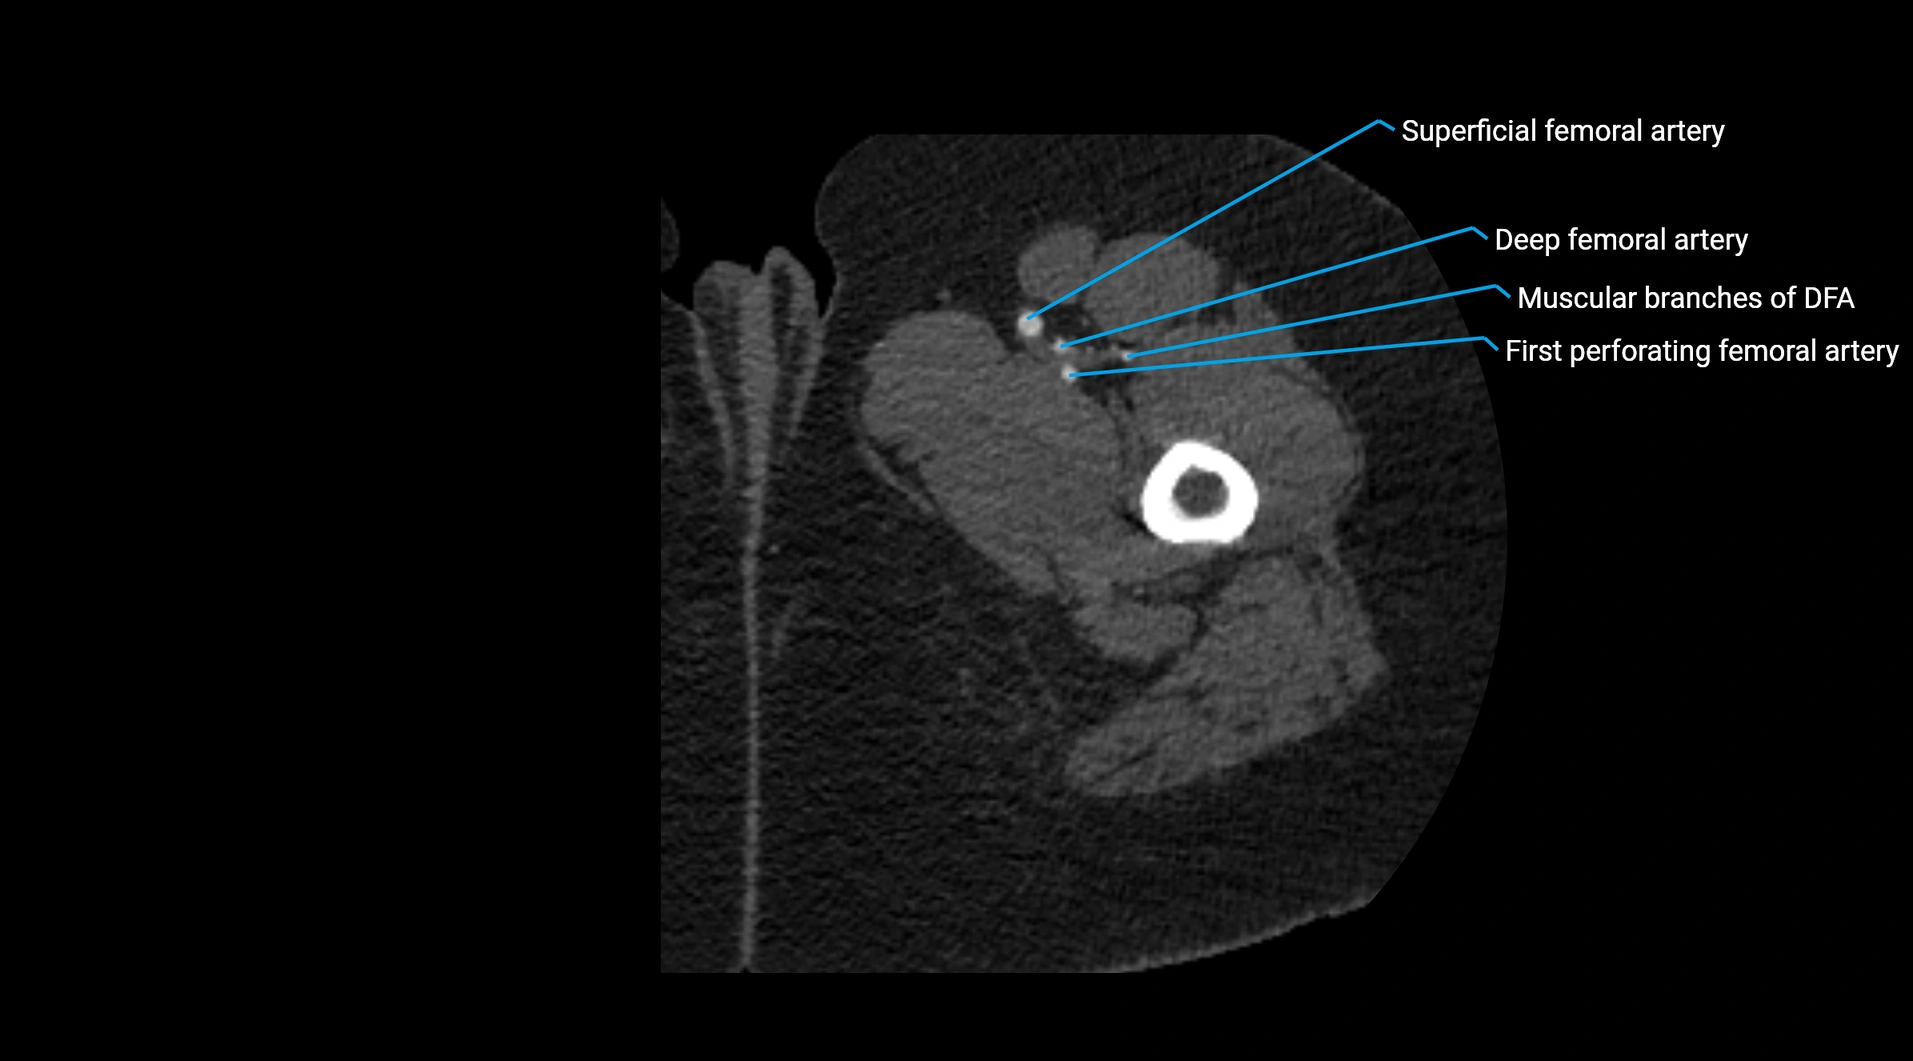

CT images

image